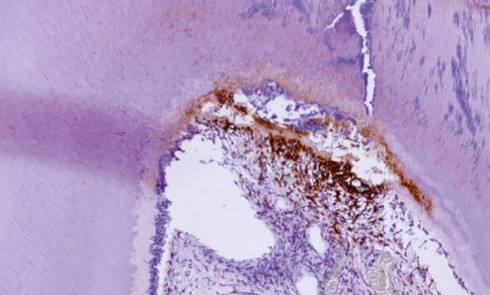

Cas 1  Motif de la consultation. Patient de 50 ans venu consulter pour la découverte fortuite par son chirurgien-dentiste d’une...